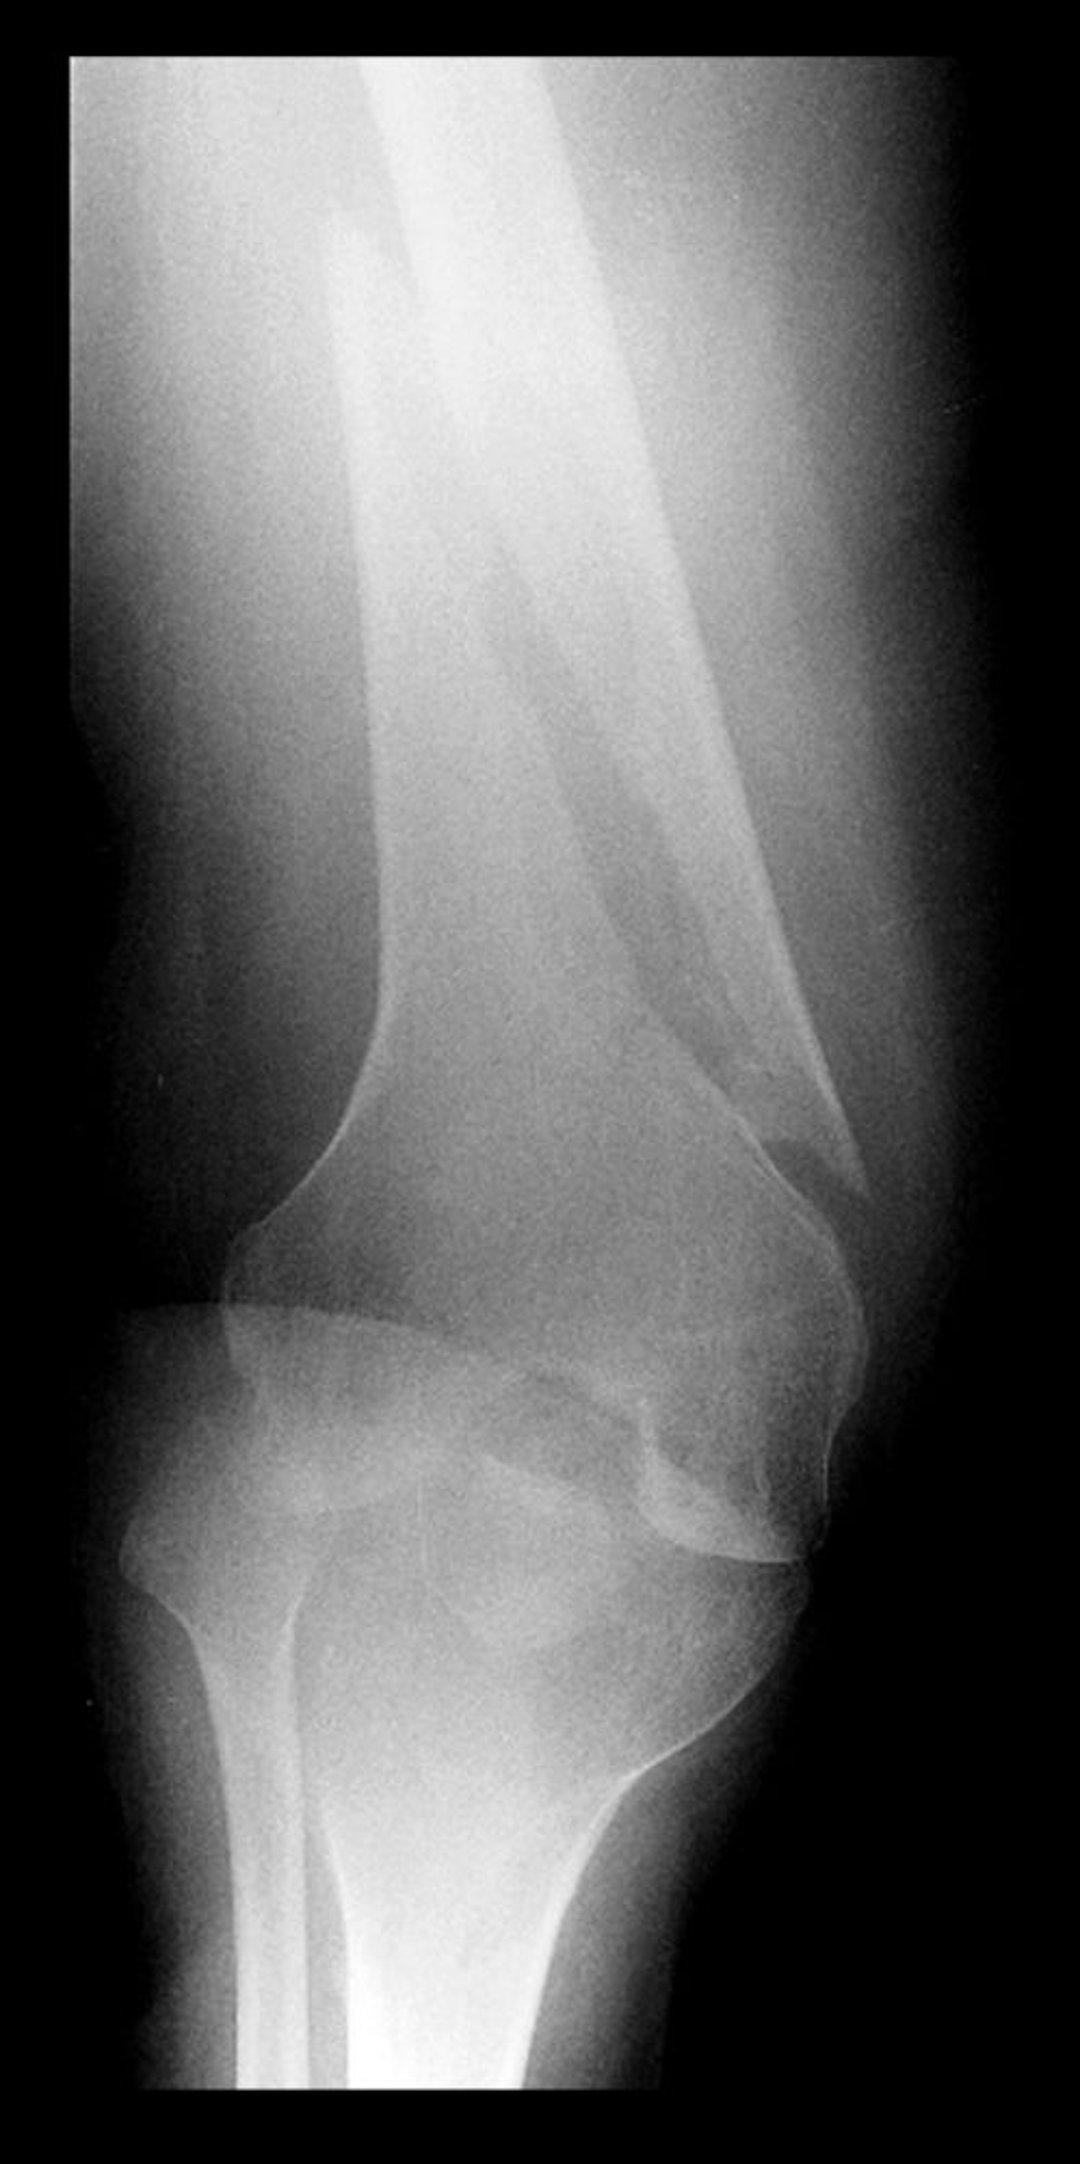

Fracture spirale du fémur distal

Cette radiographie du fémur distal montre une radiotransparence avec une composante parallèle à l'axe longitudinal de l'os, indiquant une fracture en spirale.